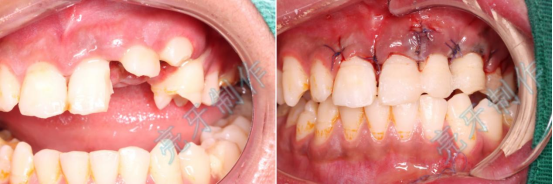

病例一:上门牙外伤,牙齿脱落;再植治疗3个月后,恢复良好。